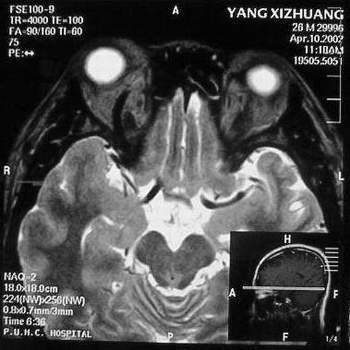

杨某,男,27岁。主因右眼进行性眼球突出一年。我院门诊就诊。发病来,患者无明显视物模糊,无视物成双。自觉无明显眼痛。五年前曾有食物中毒史。当地医院行CT检查,发现右眼眶鼻上方较高密度占位。

门诊检查:视力:双1.5。双眼各方向运动正常。右眼球向正前突出,其中颞侧更明显。右眼穹隆部结膜及近穹隆结膜血管扩张。右鼻上眶缘触及较饱满类结节物,压痛可疑。没有触及博动,听诊未及血管杂音。压迫颈静脉眼球凸度无明显改变。

B 超:球内未见明显异常回声,眶内可见血管暗影回声,视神经上下眶内周围软组织可见各一个血管暗影腔,眶内可见回声不均匀中度密度占位样回声。IMP: 眶内炎性病变?建议MRI除外动静脉瘘,血管性病变。

MRI及增强结果如下:

患者压颈及其它Valsava试验结果阴性。从MRI分析,在T1、T2、T+C检查该支血管均为明显流空现象,说明该血管血流速度很快,而从走行和分布看,眼上静脉可能性很大。也许也不能除外异常的眼动脉或异常血管。眶内主要可能的血管病变包括颈内动脉海绵窦瘘(高流窦)、AVM、眼眶静脉曲张、海绵状血管瘤、静脉性血管瘤、毛细血管瘤和眶内动脉瘤。。